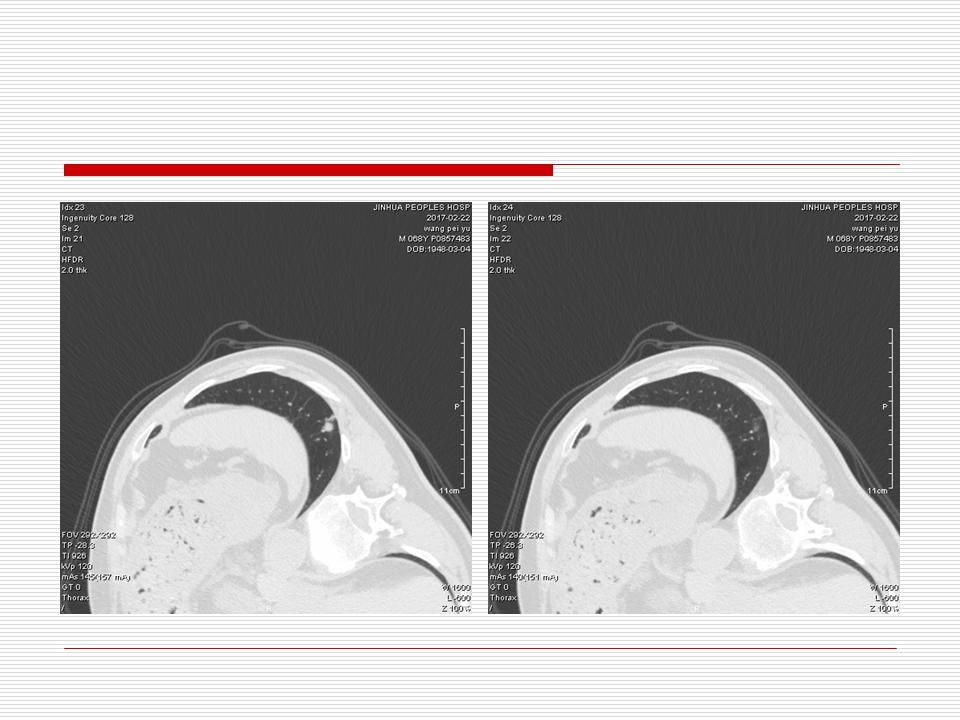

肺部阴影永恒且最重需要鉴别的是:到底是炎症还是肿瘤?但临床的病例中的影像表现难以界定或有些肿瘤特征,同时又有些炎症特点是非常常见的情况。作为临床医生我们怎么去总结分析,并找到之所以是炎症或之所以是肿瘤的细微差别或特点非常重要,也非常有用。2019.12.7浙江省2019年胸心外科学学术年会在宁波召开时,我的临床病例分析与经验总结<那些像肺癌的炎症与像炎症的肺癌>获得在大会交流的机会,以下为该PPT的内容,与你分享,希望对同道有益,有借鉴与启迪。若有探讨与进一不完善的建议,欢迎文末留言讨论: